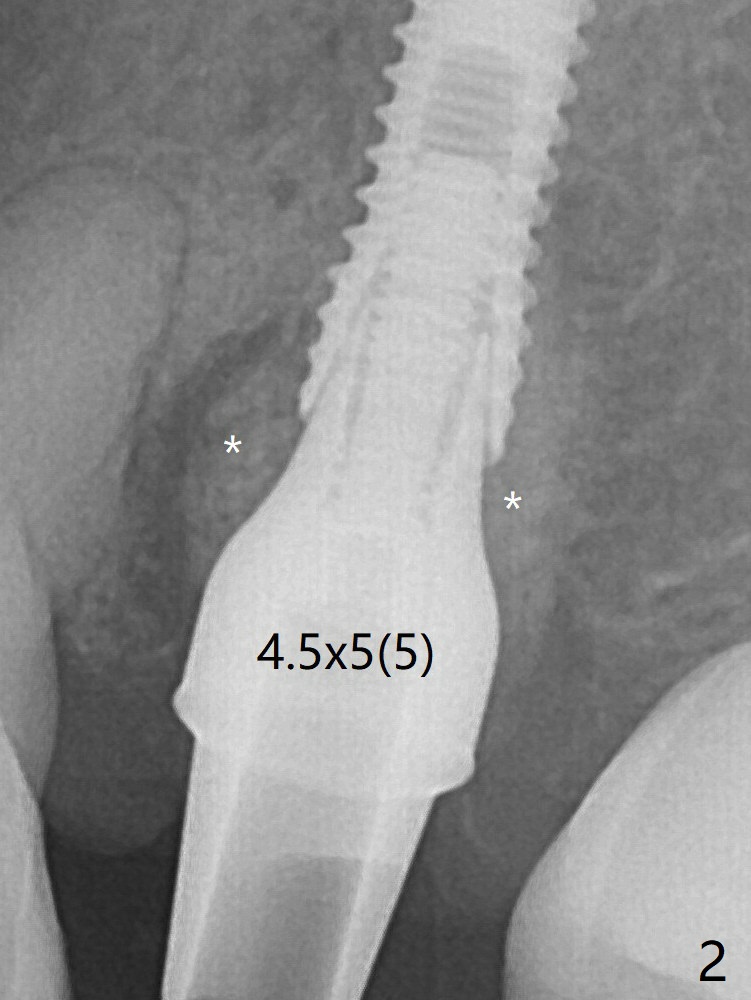

In spite of underprep osteotomy, a 3.8x18 mm implant achieves ~ 20 Ncm of insertion torque (Fig.2). When a 4.5x5(5) mm abutment is placed, it is buccal. It appears that an angled abutment is needed for final restoration (probably 4.5x15 or 25 degrees, 5 mm cuff). * Vanilla/Osteogen. The implant becomes stable 5 months postop (Fig.4), but the buccal gingiva is erythematous and tender, probably due to infected bone graft, which is removed.